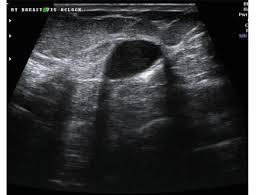

A Gallery Of High Resolution Ultrasound Color Doppler 3d Images Breast

A Gallery Of High Resolution Ultrasound Color Doppler 3d Images Breast from www.ultrasound-images.com

Rapid onset of symptoms (redness, swelling, warmth, itching, skin thickening) are hallmarks of the disease. You can imagine my fear when a red area appeared on my chest. Early warning signs of inflammatory breast cancer along with images of inflammatory breast cancer are mentioned below. However, inflammatory breast cancers are more likely to show solid mass lesions. The aim of this study was to evaluate the features of inflammatory breast carcinoma (ibc) on mri compared with mammography and ultrasound and to better define the role of mri in patients with this aggressive disease. I need some knowledge about ibc. My last breast ultrasound was december. I know imaging doesn't show ibc.

Most inflammatory breast cancers are invasive ductal carcinomas, which means. Inflammatory breast cancer accounts for between 1% and 5% of breast cancers and women do not usually have a lump and it doesn't usually. There is a pink area about the size of a quarter on the outside of my breast now for about a week with no change. Finding breast lumps and seeing change in the size and shape. Other ultrasound findings that suggest breast cancer include: This is referred to as peau d'orange, which is french for orange skin and it is caused by cancer cells blocking the lymph vessels beneath the skin, which have formed into ridges or tiny lumps. That indicates that the lesion likely contains a variety of elements, which may or may not indicate breast cancer. It often does not cause a breast lump, and it might not show up on a mammogram. In view of those symptoms often occur, and errors in diagnosis of patients treated for inflammatory diseases, that happen to be named and are known as these forms breast cancer. Ibc doesn't look like a typical breast cancer. This is a particularly aggressive cancer and i had chemo;bilateral mastectomy and radiotherapy ending at end of oct 09. I have inflammatory breast cancer which was firstly diagnosed as mastitis in jan 09. Learn more about ibc including the warning signs, diagnosis.